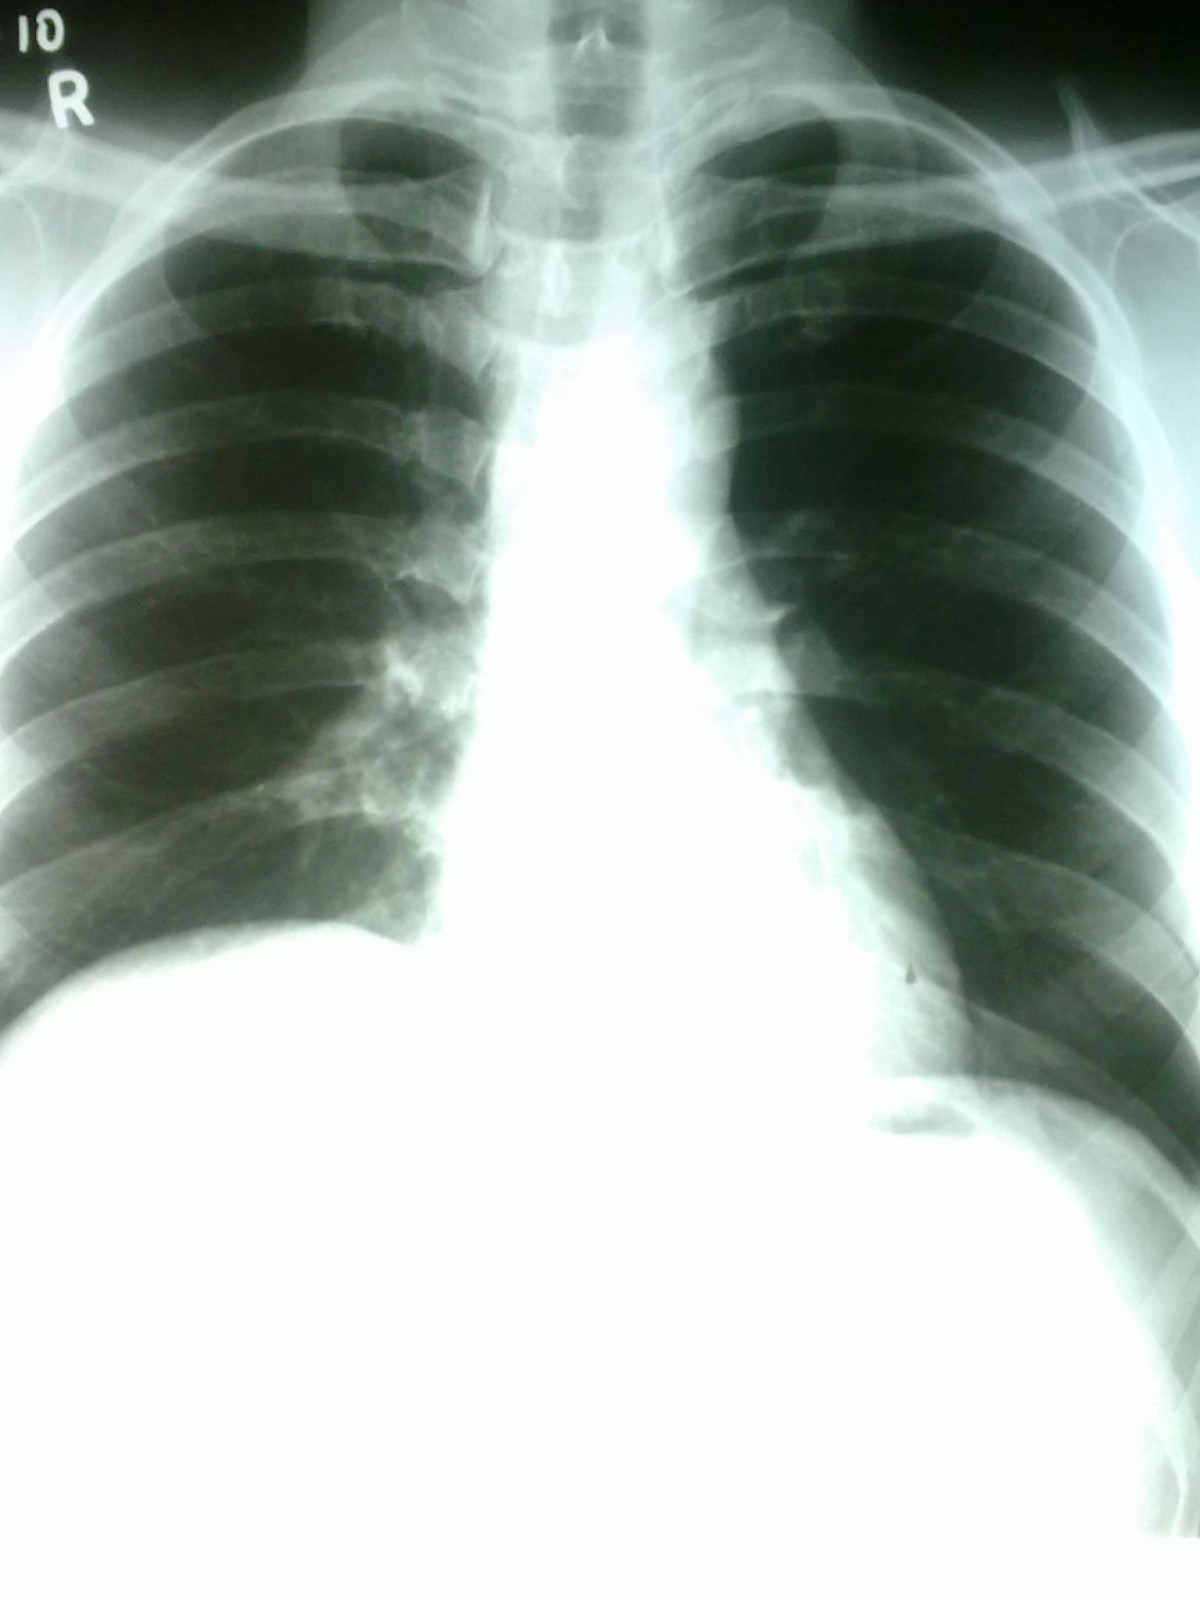

A 40yearold woman with dengue hemorrhagic fever. Chest Xray (a)... Download Scientific Diagram Chest X Ray For Dengue Severe dengue fever is characterized by marked thrombocytopenia, severe hemorrhage, plasma leakage leading to. Diffuse alveolar hemorrhage (dah), commonly defined as the association of hemoptysis, new pulmonary infiltrates on chest. Chest radiographs showed normal findings in 9 out of the 21 patients. The most frequently used imaging methods in dengue are chest radiography and abdominal ultrasound, especially in emergency. Chest X Ray For Dengue.

Pleural effusion A six years old boy with Dengue shock syndrome. The... Download Scientific Chest X Ray For Dengue The most frequently used imaging methods in dengue are chest radiography and abdominal ultrasound, especially in emergency. Severe dengue fever is characterized by marked thrombocytopenia, severe hemorrhage, plasma leakage leading to. Diffuse alveolar hemorrhage (dah), commonly defined as the association of hemoptysis, new pulmonary infiltrates on chest. Chest radiographs showed normal findings in 9 out of the 21 patients. Chest X Ray For Dengue.